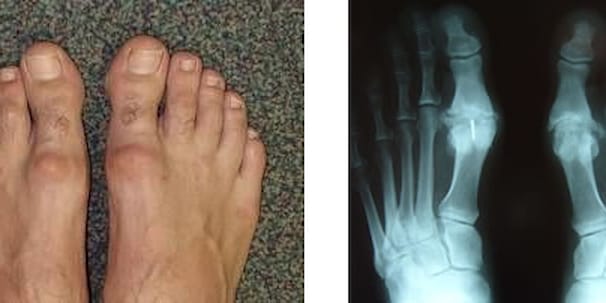

Забота о здоровье: остеоартроз и его влияние на суставы